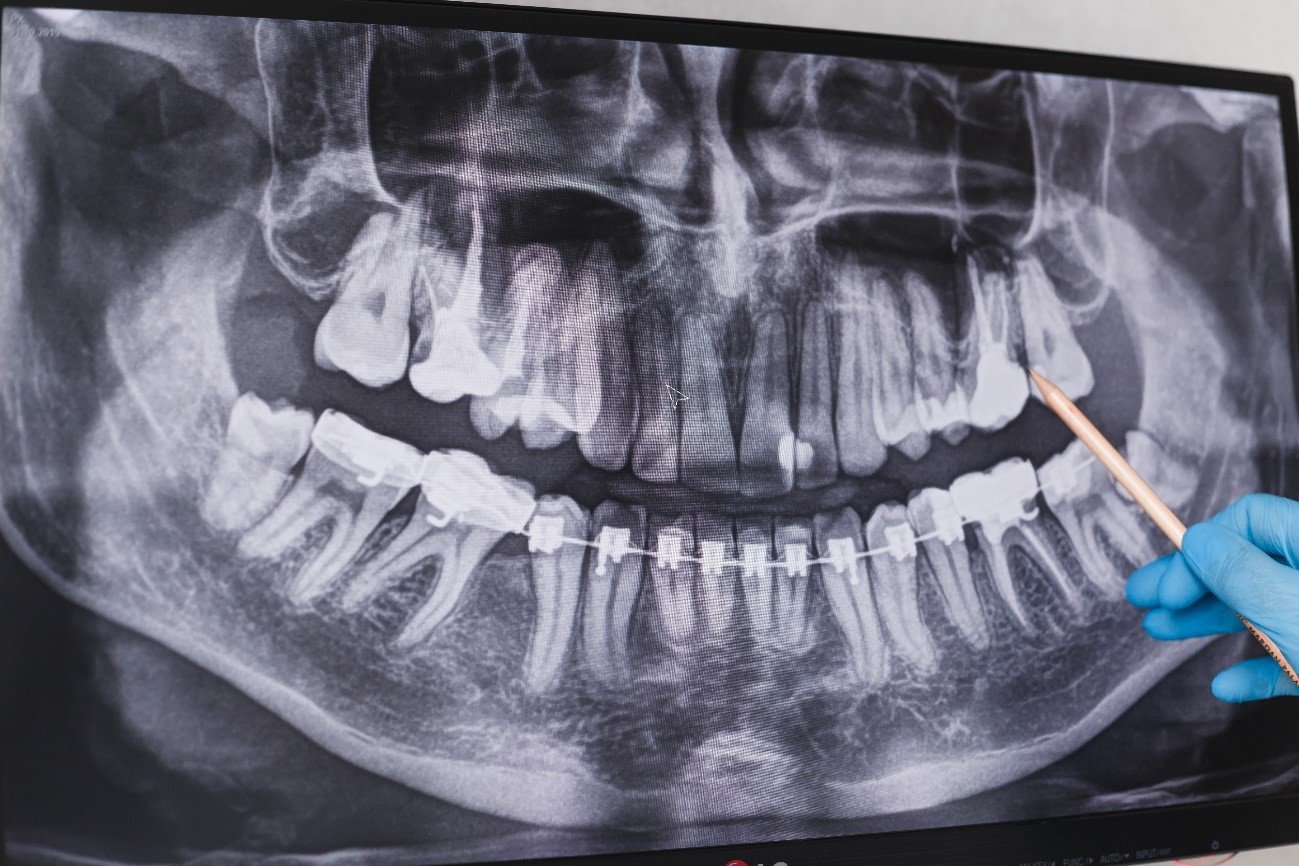

Las muelas del juicio son el tercer juego de molares ubicados en la parte posterior de la boca. Por lo general, comienzan a salir en la adolescencia, aunque también pueden salir en la adultez temprana. En total, la mayoría de las personas tienen cuatro muelas del juicio (aunque no siempre salen las cuatro), dos en la mandíbula superior y dos en la mandíbula inferior. Estas muelas son llamadas “del juicio” porque, a diferencia del resto de la dentición definitiva que se forma durante la infancia, estas suelen aparecer en una etapa de la vida en la que las personas están más maduras y, tienen “más juicio o sabiduría”.

- Apiñamiento dental: La erupción de las muelas del juicio puede ejercer presión sobre los dientes adyacentes, causando apiñamiento dental y desalineación.